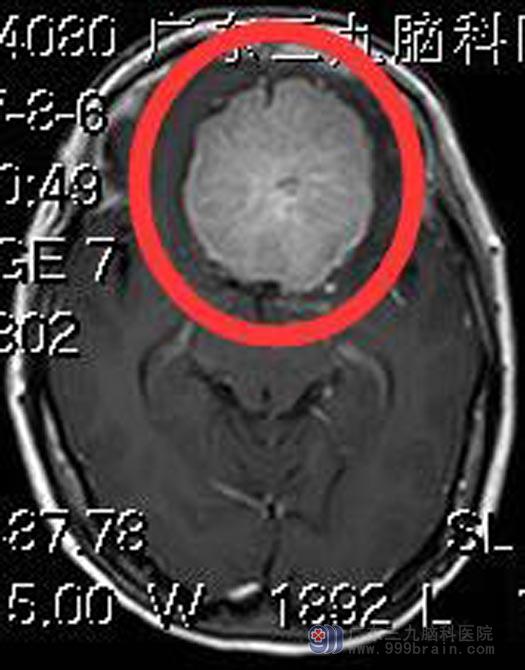

一个月前她感觉头痛较之前加重,伴有头晕、视物模糊。广东三九脑科医院头颅CT检查,示“前颅窝底占位,考虑脑膜瘤”。进一步头颅MR检查,结果提示:前颅窝底占位,大小约5.9cm×5.3cm×3.9cm,考虑脑膜瘤。头颅CTA检查提示:前颅窝底示一较大占位性病变,边界清晰,大小约为5.34cm×4.90cm×4.0cm,其内示多条粗细不等血管影,邻近双侧大脑前动脉受压上抬及右偏,左侧大脑中动脉轻度受压,邻近颅底骨质明显增生。